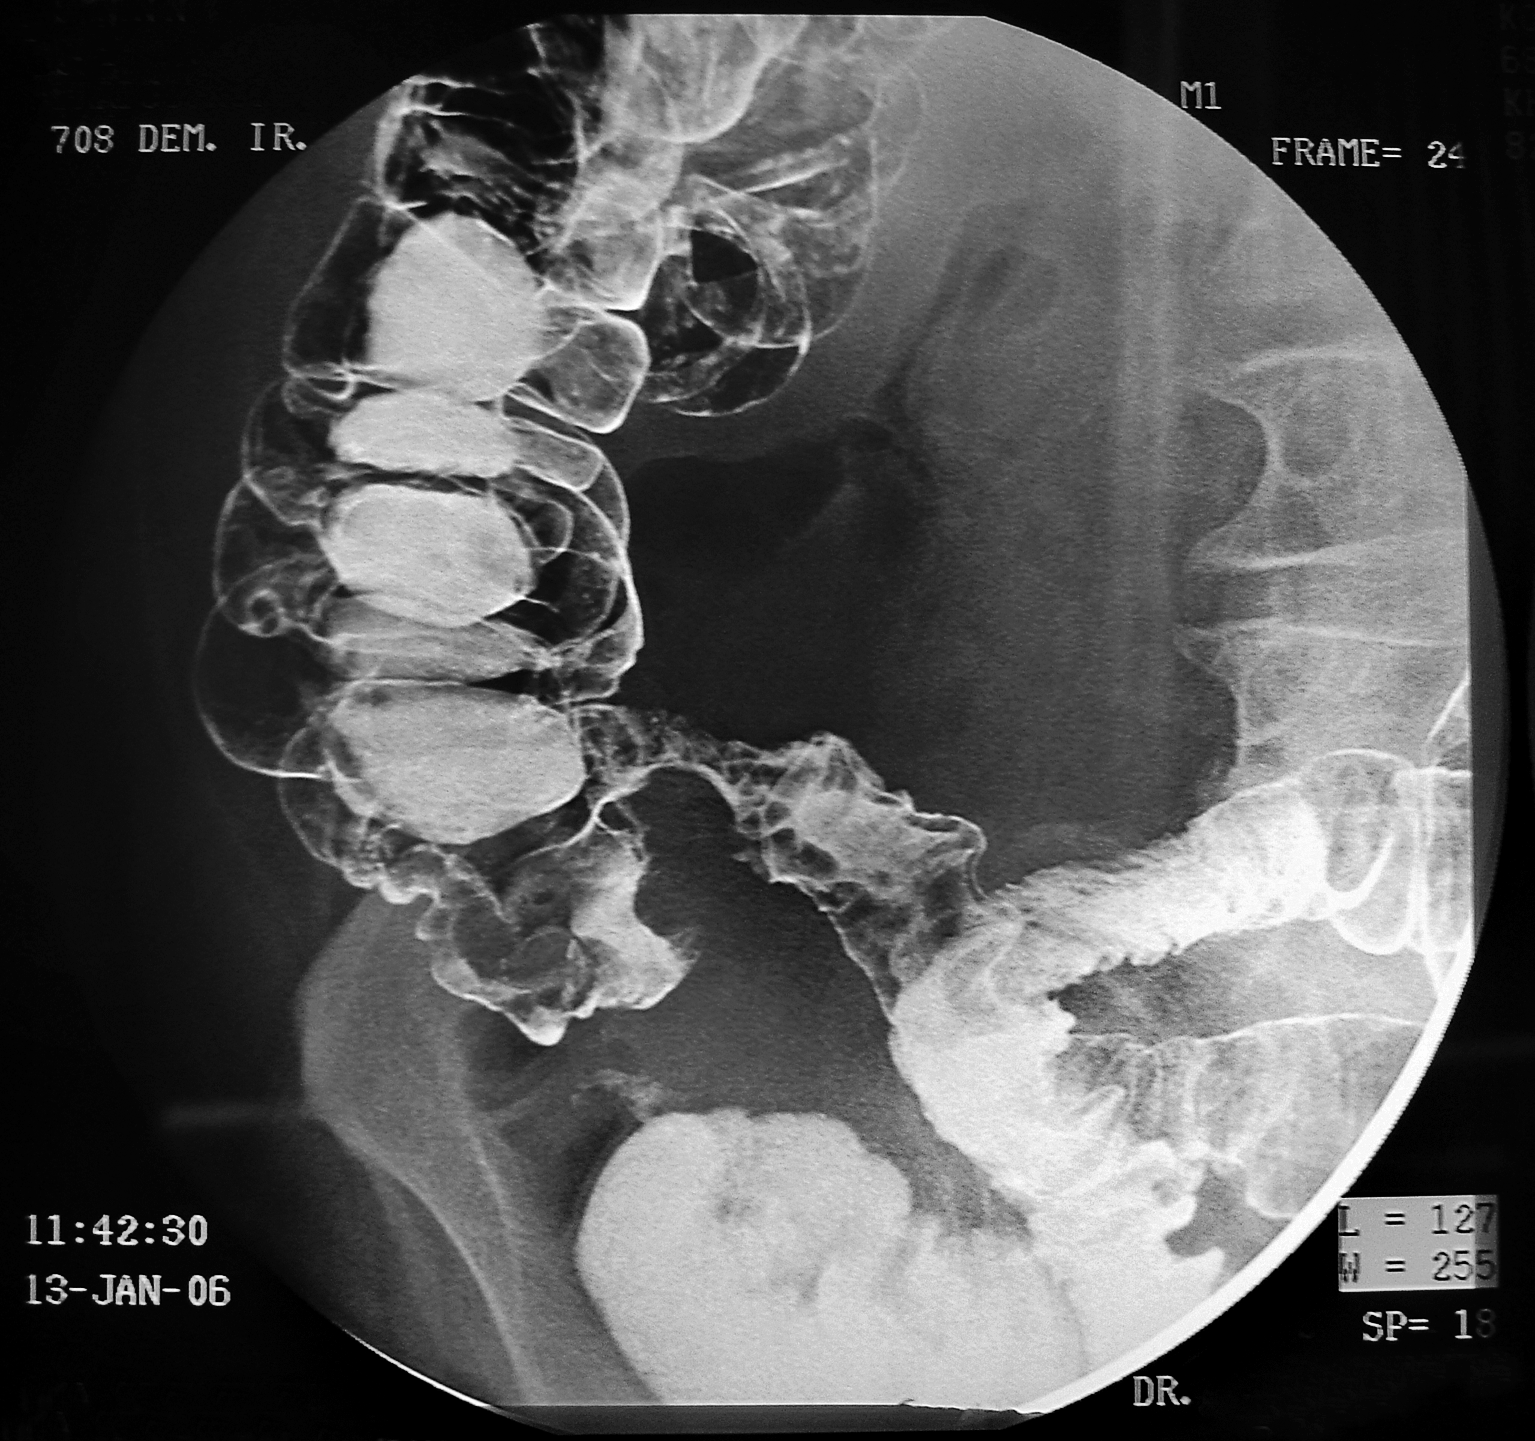

Современные технологии в медицине: рентгенодиагностика заболеваний желудка